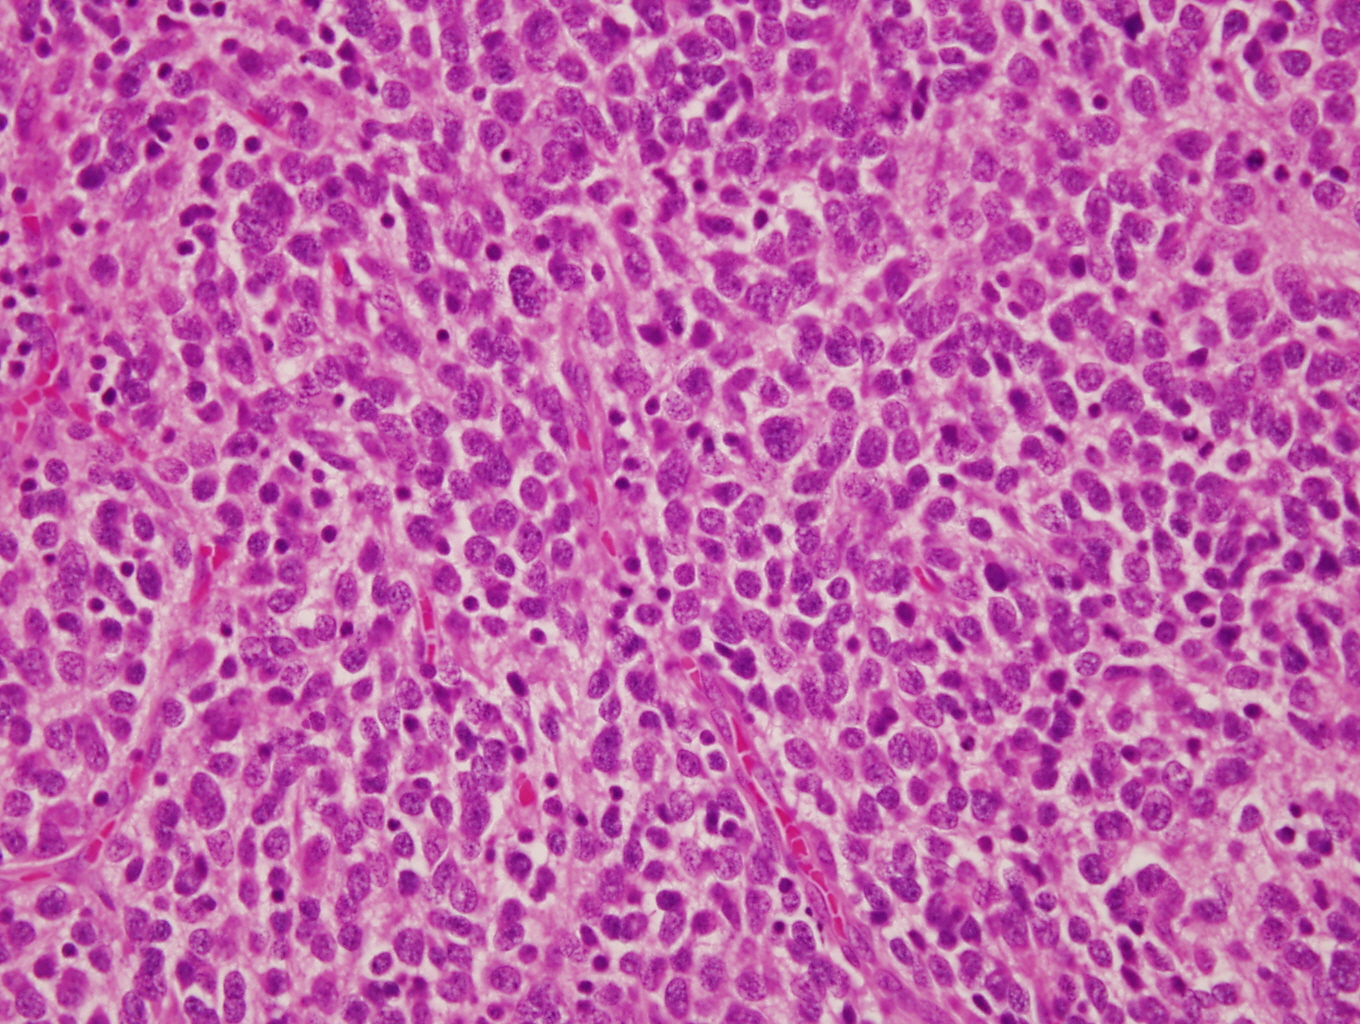

- Architecture: lobular, diffuse / solid, organoid

- Neuroblasts

- Homer Wright pseudorosettes = circular, ovoid, angular zones of pale staining neuritic cell processes surrounded by tumor cell nuclei; may rarely palisade

- Minimal cytoplasm, may have cytoplasmic tail

- Round to ovoid nuclei with stippled salt and pepper chromatin, inconspicuous nucleoli

Intermixed type